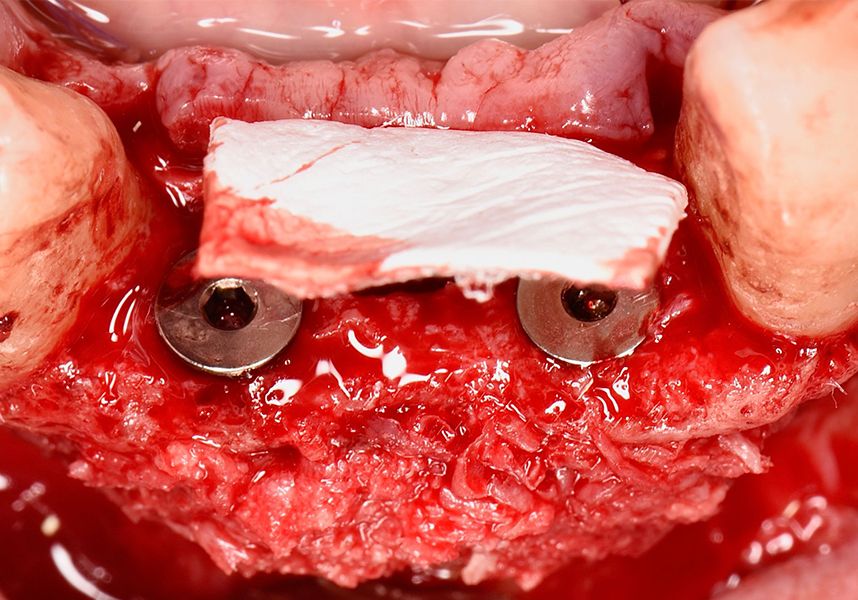

To treat the defect, bone regeneration was carried out simultaneous to the surgical process, with an autologous bone graft from the patient. In the internal part of the graft we used autologous cortical bone obtained by scraping (Safescraper) and from the biological drilling, at low revolutions and without irrigation, from the other implant beds. In the external layer of the regeneration we used a xenograft (Genoss, Osteogenos) and this was covered with a reabsorbable collagen barrier membrane (Evolution STD, Osteogenos).

The membrane was sutured with PGA reabsorbable suture to the periosteum to secure it, thus avoiding subsequent reentry to remove fixings such as tacks.